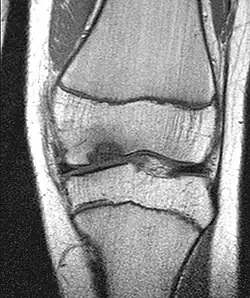

Die Erkrankung kann zufällig auf einem Röntgenbild entdeckt werden, das nach einem Unfall von der Knieregion, vom Sprunggelenk oder vom Ellbogen angefertigt wird. Bei typischen Beschwerden von aktiven Kindern und Jugendlichen kann mit einem solchen einfachen Röntgenbild die eindeutige Diagnose schon gestellt werden, weil der veränderte Knochen unterhalb der Gelenkoberfläche an typischer Stelle in der Oberschenkelrolle am Knie identifiziert werden kann. Manchmal kann eine sogenannte Tunnelaufnahme mit gebeugtem Knie die Schädigungszone noch besser zeigen. Zur genaueren Analyse sollte eine Kernspintomographie (MRT) durchgeführt werden. An den dabei erzeugten Bildern lässt sich die Lage und Größe des Befundes, die Tiefenausdehnung und vor allem eine Beteiligung des darüberliegenden Knorpels genau ausmessen. Es sind damit auch Aussagen zur Stabilität des Befundes zu treffen. Daraus ergeben sich dann entscheidende Anhaltspunkte für therapeutische Konsequenzen. Für die Verlaufsbeurteilung der Erkrankung eignet sich am besten das MRT, aber ggf. auch wieder die einfache Röntgenuntersuchung. Aufgrund der extrem hohen Kosten für das MR in den USA werden die Verläufe dort bis heute weitgehend nur mit Röntgenbildern dokumentiert, was zu eigenen Empfehlungen zur Verlaufsbeurteilungen führt. Generell wären aber die MR-Untersuchungen das Verfahren der Wahl. Sie erlauben eine differenzierte Beurteilung der unterschiedlichen Kriterien für Ausheilung, Instabilität und drohende Dissektion. Untersuchungen mit Sonographie können zuverlässige, aber nur orientierende Befunde am Femurkondylus erheben. Es ist damit zum Beispiel ein schneller, kostengünstiger und sicherer Ausschluss des Befalls auch der Gegenseite möglich.

Derselbe Patient: Großer Gelenkflächendefekt nach Dissektion des oben dargestellten OD-Herdes im Kernspinbild

Die Therapie der Osteochondrosis dissecans am Kniegelenk ist zunächst abhängig von der relativen Größe der Läsion im Vergleich zur Kondyle. Es gibt OCD an der medialen und an der lateralen Oberschenkelrolle (Kondyle). Selten kommt die Veränderung auch am Gleitlager gegenüber der Kniescheibe und an der Kniescheibe selber vor. Ein weiteres wichtiges Entscheidungskriterium ist das Stadium (stabil / instabil) der Läsion. Als Instabilitätszeichen tritt im MRT eine Zystenbildung, eine Vorwölbung des Knorpel-Knochen-Dissekates, ein Bruch der subchondralen Knochenlamelle und eine Rissbildung im Knorpel deutlich hervor. Ein wichtiges klinisches Symptom einer Instabilität des OD-Herdes ist eine Blockierung in der Gelenkfunktion, die als Zeichen der Beteiligung der Gelenkfläche an dem Erkrankungsprozess auftreten. Zusätzlich spielt das Alter des Patienten eine gewisse Rolle. Bei noch weit offenen Wachstumsfugen – also bei Jungen bis zum 14. und bei Mädchen bis zum 13. Lebensjahr – sind die spontanen Heilungsaussichten besser. Im Durchschnitt heilen bei allen Studien ca. 50 % der OCD-Fälle am Kniegelenk ohne operative Maßnahmen aus. Die komplette Ausheilung erfordert immer Monate bis Jahre, weil der notwendige Knochenumbau (Remodeling) durch Osteoklasten und Osteoblasten lange Zeit in Anspruch nimmt. Hierzu müssen ja knöcherne Strukturen aufgelöst, abtransportiert und wieder aufgebaut werden. Die therapeutischen Maßnahmen können aber je nach Fortgang der Heilung schon vor dessen komplettem Abschluss beendet werden.

Bei anhaltenden oder trotz konsequenter Sportpause zunehmenden Beschwerden am Knie oder Sprunggelenk, besonders bei Neuauftreten von mechanischen Symptomen wie Blockierungen und bei Größenzunahme oder Instabilitätshinweisen im MRT ist eine Gelenkspiegelung (Arthroskopie) des betreffenden Gelenkes empfohlen, um den Zustand des Gelenkknorpels beurteilen zu können, was mit der Kernspintomographie nicht zuverlässig gelingt. Harte Kriterien für eine Operation sind ein großer Herd, Zystenbildungen über 2,3 mm und Instabilitätszeichen im MR und natürlich sogar für eine notfallmässige Operation eine stattgehabte Dissektion (Lösung).